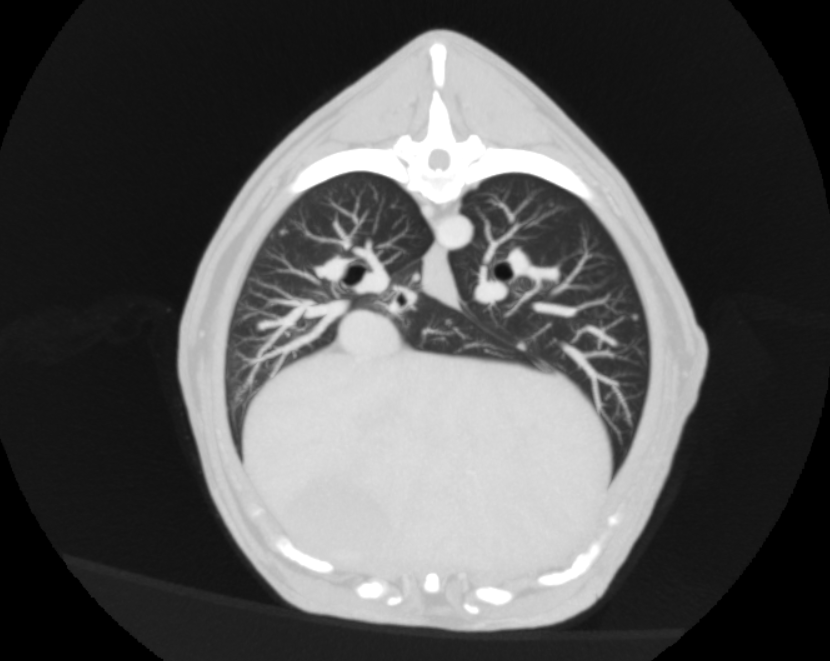

Imagen descriptiva